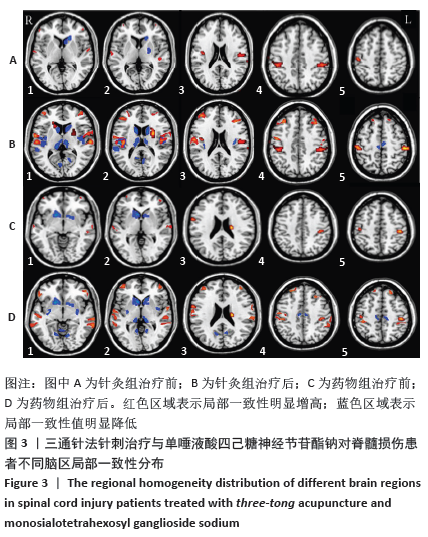

[32] RAO JS, MA M, ZHAO C, et al. Alteration of brain regional homogeneity of monkeys with spinal cord injury: A longitudinal resting-state functional magnetic resonance imaging study. Magn Reson Imaging. 2015;33(9):1156-1162.

[33] ZHU L, WU G, ZHOU X, et al. Altered spontaneous brain activity in patients with acute spinal cord injury revealed by resting-state functional MRI. PLoS One. 2015;10(3):e0118816.

[34] HOU JM, SUN TS, XIANG ZM, et al. Alterations of resting-state regional and network-level neural function after acute spinal cord injury. Neuroscience. 2014;277:446-454.

[35] RAO JS, MA M, ZHAO C, et al. Fractional amplitude of low-frequency fluctuation changes in monkeys with spinal cord injury: a resting-state fMRI study. Magn Reson Imaging. 2014;32(5):482-486.